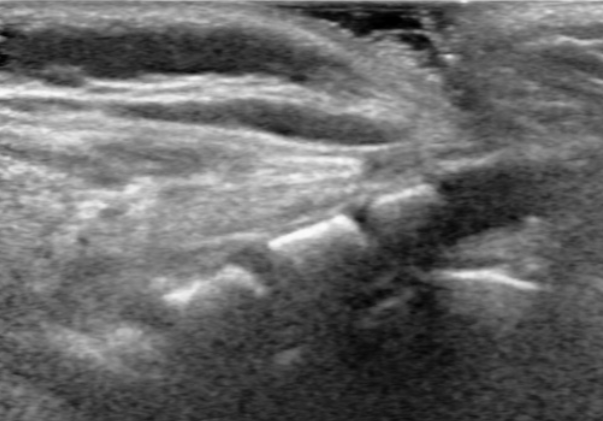

Developmental Dysplasia of the Hip (DDH): Diagnostic Imaging with Ultrasound vs. X-Ray

Learn the pros and cons of physical exam maneuvers, high risk features, and diagnostic imaging pearls for suspected developmental dysplasia of the hip (DDH).